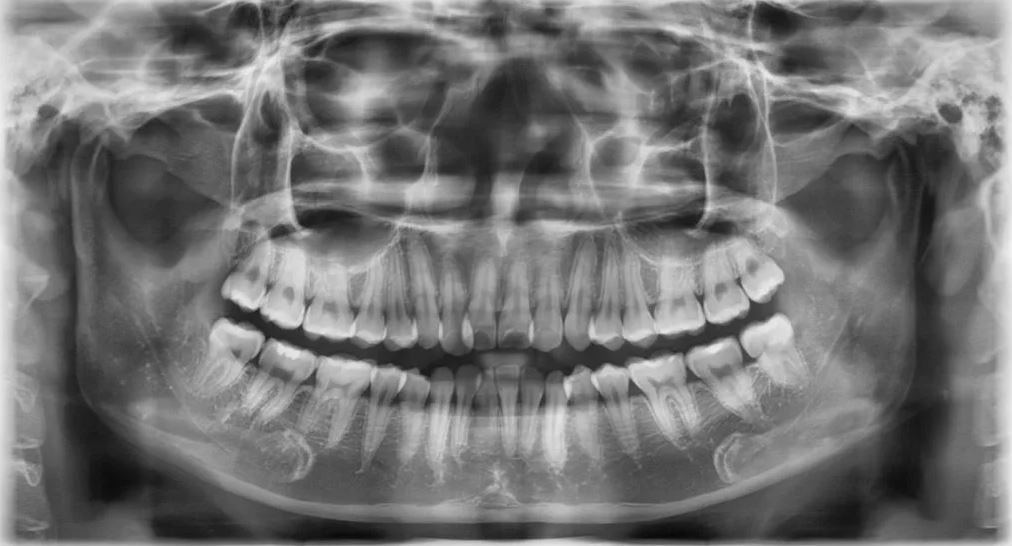

Để thực hiện niềng răng các bác sĩ phải lên phác đồ điều trị cụ thể đối với từng trường hợp. Để có thể chẩn đoán chính xác và lên kế hoạch điều trị hợp lý, bác sĩ phải hiểu rõ đặc điểm xương hàm, trục răng, mức độ lệch lạc của răng và độ cứng chắc của răng như thế nào... Do vậy chụp Xquang trước kh niềng rang là việc rất cần thiết. Thông qua những hình ảnh thu được từ việc chụp phim Xquang khi niềng răng kết hợp với hình ảnh thăm khám khoang miệng, ngoài mặt, lấy dấu mẫu hàm, bác sĩ mới có thể đưa ra được những nhận định và phán đoán chính xác về tình trạng răng, hướng dịch chuyển của răng sau khi niềng và lên phác đồ cụ thể cho từng trường hợp.

Niềng răng trong chỉnh nha là một điều trị trong khoảng thời gian dài, từ 2 - 3 năm, điều này có thể khiến bác sĩ không thể nhớ hết được những điều trị của mình cũng có thể bệnh nhân sẽ quên đi hàm răng trước khi niềng của bản thân. Vì vậy việc chụp Xquang sẽ cho phép bác sĩ và bệnh nhân có cái nhìn toàn diện và chính xác hơn trong quá trình niềng răng.

Bên cạnh đó, chụp phim Xquang là một trong những cách lưu trữ thông tin về tình trạng răng và xương hàm của bệnh nhân, dựa vào các hình ảnh trên phim qua các lần chụp bác sĩ và bệnh nhân có thể thấy được sự di chuyển của răng cũng như hiệu quả quá trình điều trị chỉnh nha.

Chụp phim X-quang là một phần không thể thiếu trong quá trình niềng răng. Các loại phim khác nhau giúp bác sĩ nha khoa có được những thông tin quan trọng để theo dõi và điều chỉnh liệu trình niềng một cách tối ưu, đem lại kết quả tốt nhất cho bệnh nhân. Liên hệ SHINING SMILE qua hotline: 039775 8888 Địa chỉ tại Số 47 Khúc Thừa Dụ, Q. Cầu Giấy, TP. Hà Nội để được hỗ trợ thêm.